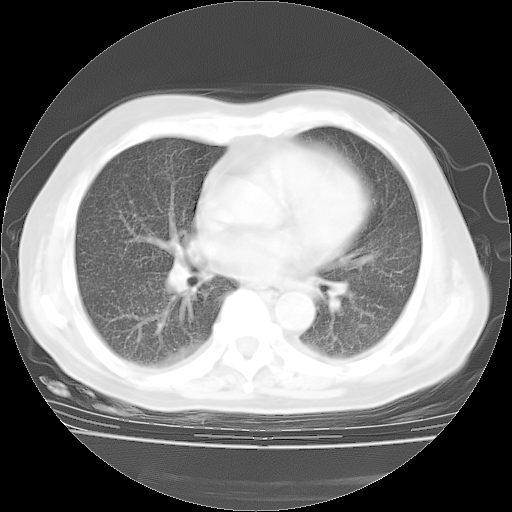

4月28日肺部CT——再次出现类似去年5月9日——透光度降低,“间质性”改变。

4月28日肺部CT——再次出现类似去年5月9日——磨玻璃样、间有“粟粒样”改变。

4月28日肺部CT

1、108#的是4月14日的胸部CT(发此贴时还没看着28日的CT)。14日的胸部CT其实已经出现改变(如108#所述),个人认为28日的胸部CT除纵膈窗疑似有双侧胸膜增厚或少量胸积液(可行胸部B超明确)外,与4月14日对照病变有所加重;2、已经给予“异烟肼、利福平、乙胺丁醇”抗痨治疗?如果是,甲强龙80mg可缓慢减量;如果环磷酰胺已停用,暂不使用;3、中性粒细胞92%,明显升高,目前体温情况?注意合并细菌感染可能,使用左氧氟沙星情况下,是否联用B-内酰胺类抗菌药物?另外是查免疫全套非风湿全套。

今请临免主任会诊后认为:4月14日胸部CT已有双下肺间质性改变。患者病情复发多系激素减量过快不正规所致。目前甲强龙80mg/日,一周后酌情开始减量,不易过快。环磷酰胺若已停用,暂不使用。他同意目前抗菌药物使用,但应考虑是否加用B-内酰胺类抗菌药物(中性细胞明显增高);2、结核复发目前依据不足;3、若免疫全套各项指标正常,考虑多系特发性肺间质炎可能大。4、加强支持,并注意保护胃黏膜。